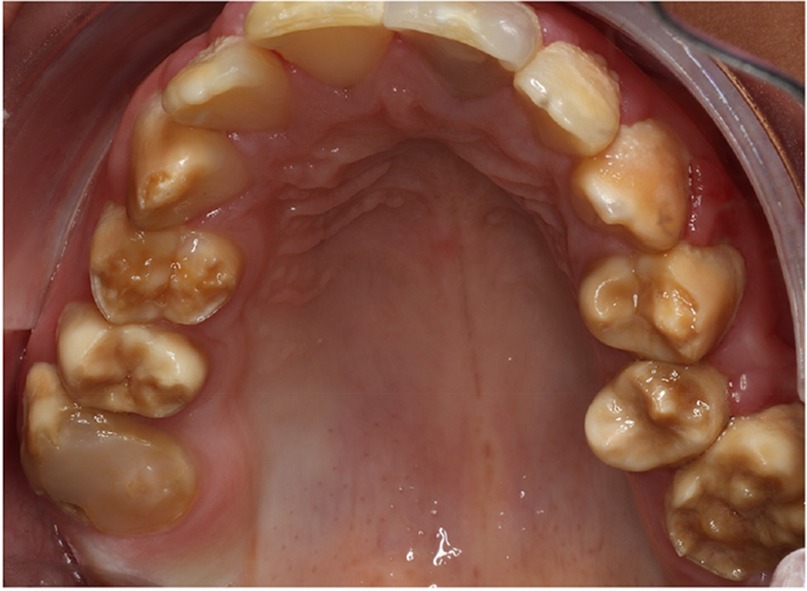

There was a mistake in Figure 1 as published. The image of the maxillary arch has been positioned upside down. The corrected Figure 1 appears below.

Figure 1

Figure 1. A typical Poly AI patient with maxillary hypomineralised dentition exhibiting mottled yellow and brown discolouration.